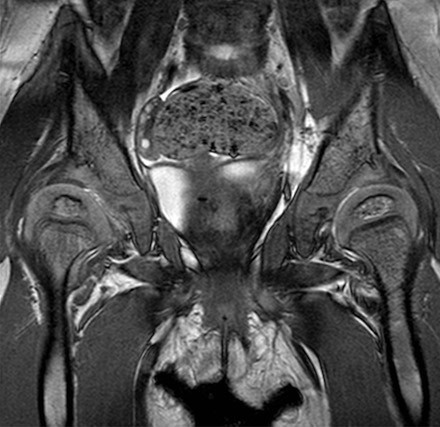

Wat is een MRI-scan?

Een MRI-scan is een scan die wordt gemaakt met behulp van een magneetveld en radiogolven. MRI staat voor Magnetic Resonance Imaging. Met een MRI-scan is het mogelijk om de weke delen van een gewricht (alles behalve het bot) in beeld te brengen waardoor bij de heup bijvoorbeeld ook het labrum en het kraakbeen van het gewricht kunnen worden bekeken.

MRI van een kind van twee jaar. Dwarsdoorsnede door beide heupgewrichten: het kraakbeen van de heupkoppen is goed zichtbaar. Op een röntgenfoto is dit niet te zien.

Soms wordt ook gebruik gemaakt van contrastvloeistof om het beeld nog duidelijker te krijgen. Dit kan worden ingespoten met behulp van een infuus in de arm of rechtstreeks in het gewricht. Dit laatste wordt een arthrogram genoemd.

Omdat een MRI-scan wordt gemaakt met behulp van een magnetisch veld verstoren metalen het beeld dat de scan maakt. Dit betekent echter niet dat er geen MRI-scan kan worden gemaakt als je bij een eerdere operatie schroeven of een kunstheup hebt gekregen. Bij het maken van de scan kan men met een speciaal programma de effecten van deze voorwerpen zo klein mogelijk maken. Daarnaast zal je arts er bij het aanvragen van de scan al rekening mee houden dat sommige dingen wellicht niet goed te zien zullen zijn.